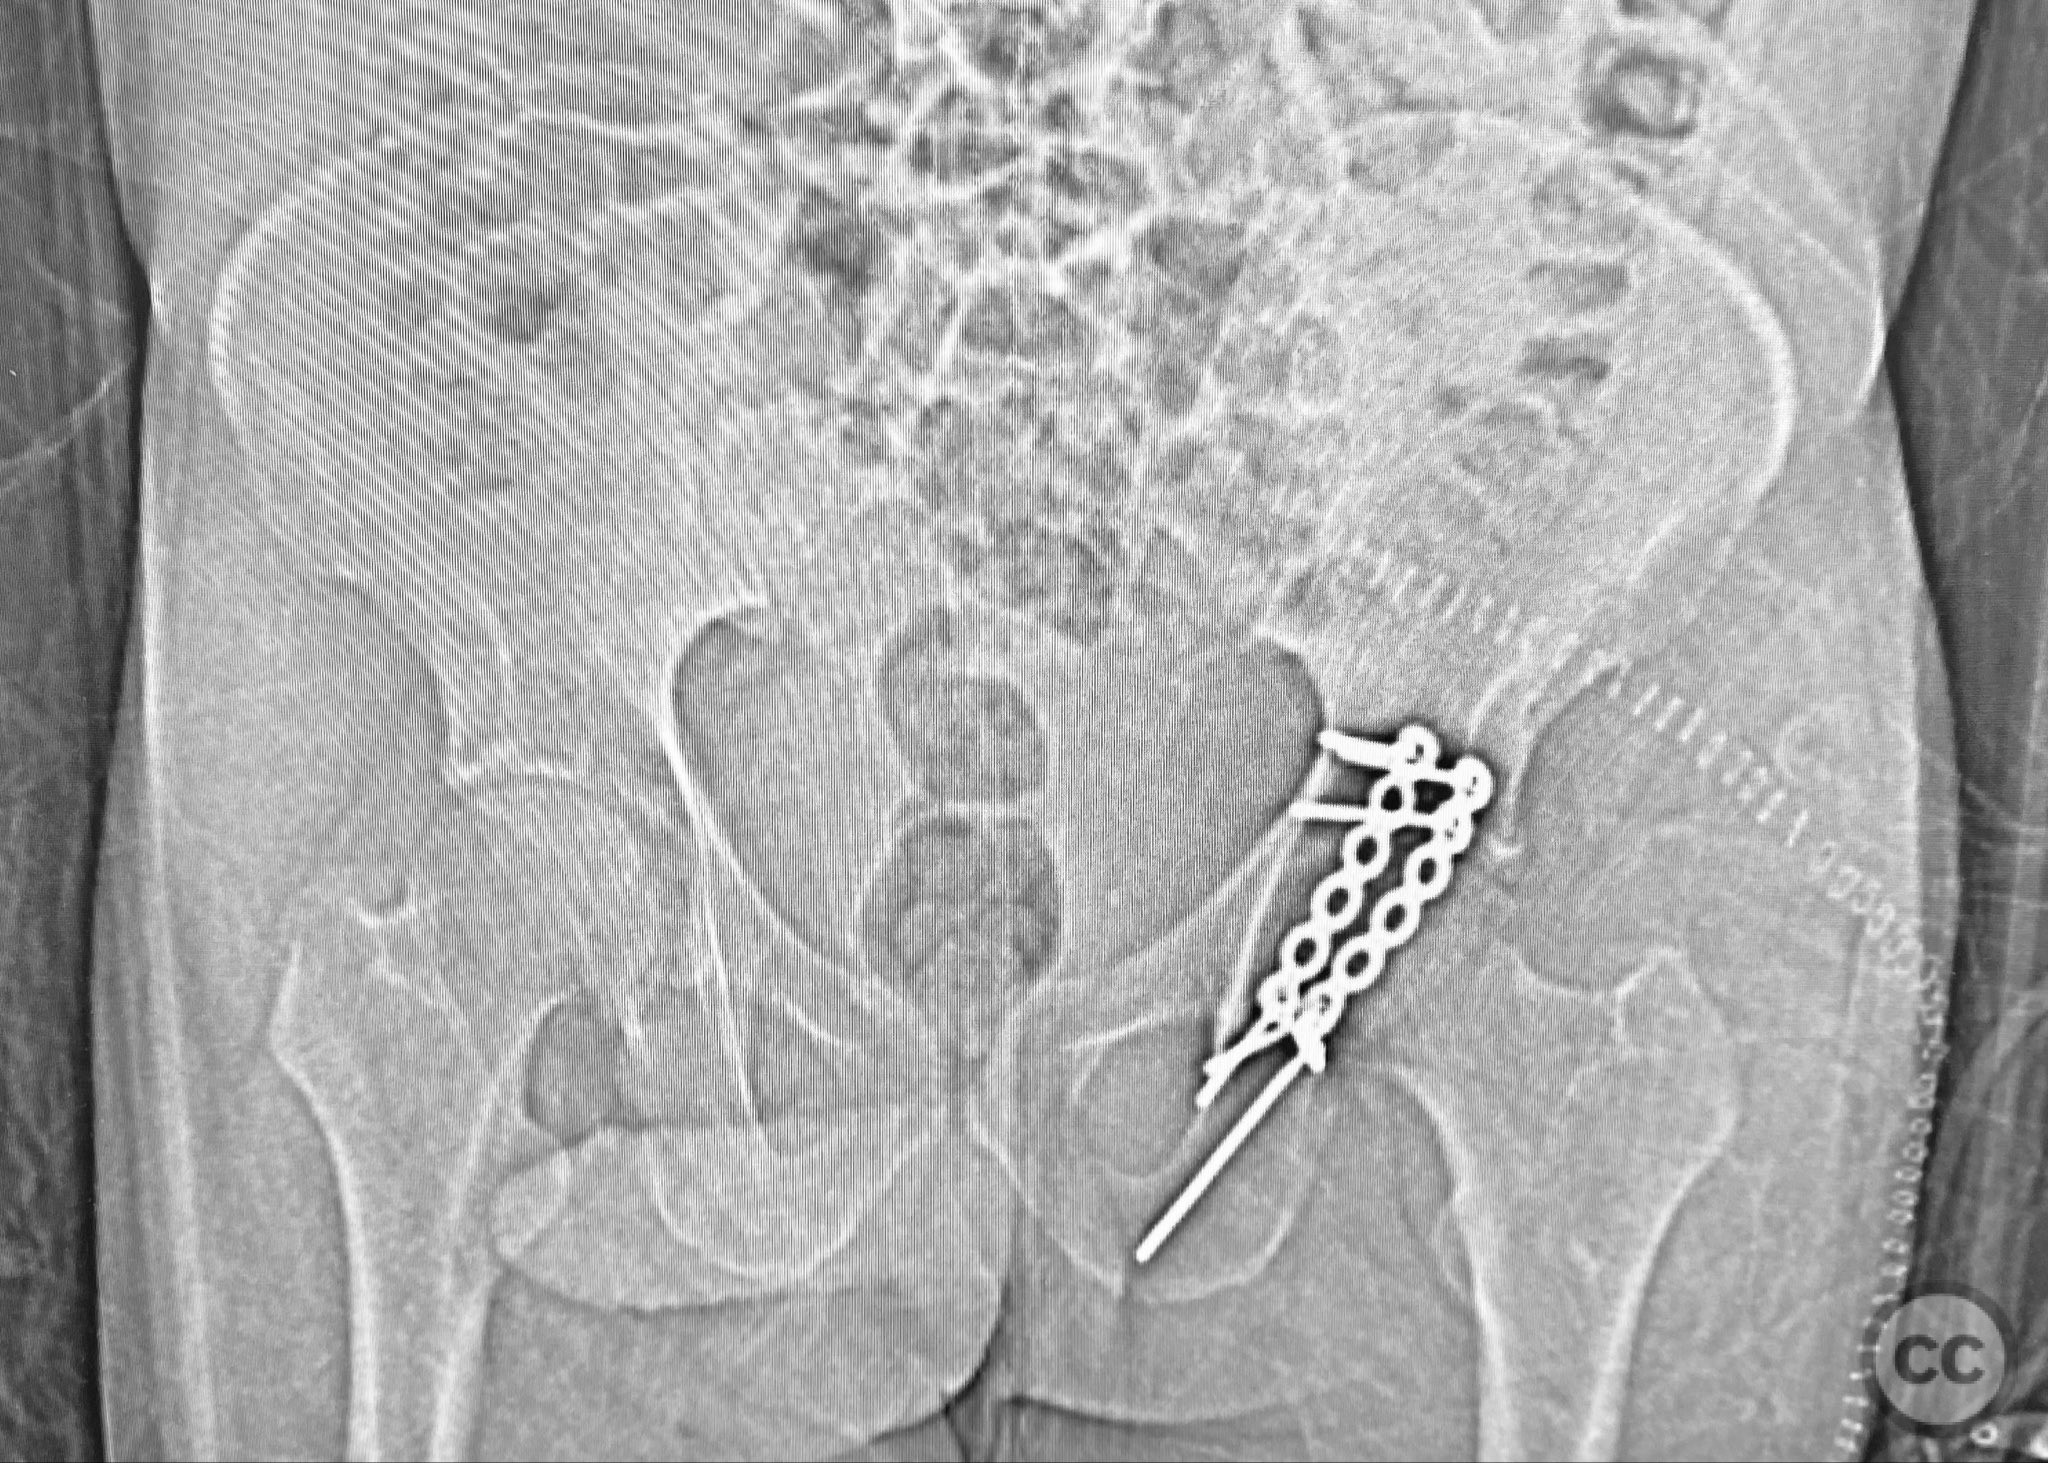

Clinical and radiological findings:  A patient presented with a seemingly non-comminuted, wide, and long posterior wall (PW) acetabular fracture fragment. Axial computed tomography (CT) images demonstrated the thickness of the PW fragment, the articular surface, and multiple areas of subchondral impaction. Preoperative planning identified the size, location, and depth of the impaction zones, as well as an essentially nondisplaced transverse acetabular fracture line, which was not readily apparent on initial imaging. No significant displacement of the transverse component was noted. The AO/OTA classification is 62-B1.3 (posterior wall and transverse acetabular fracture).

Intraoperatively, elevation and reduction of impacted articular fragments were performed, followed by bone grafting of subchondral defects. The posterior wall fragment was anatomically reduced and initially stabilized with a contoured plate. Intraoperative fluoroscopy (obturator oblique view) was utilized to guide placement of an additional screw through the plate above the joint, traversing both the posterior wall fragment and stabilizing the transverse fracture line. A supplementary medial plate was applied to further support both fracture components. Postoperative CT imaging confirmed satisfactory reduction of both the posterior wall and transverse fractures, as well as restoration of articular congruity in previously impacted areas. Consideration is given to whether initial reduction and lag screw fixation of the transverse component prior to plate application may have improved reduction; however, final imaging demonstrated acceptable alignment.

Orthopaedic implants used:   3.5 mm pelvic reconstruction plates (posterior wall and medial), 3.5 mm cortical screws, autologous bone graft